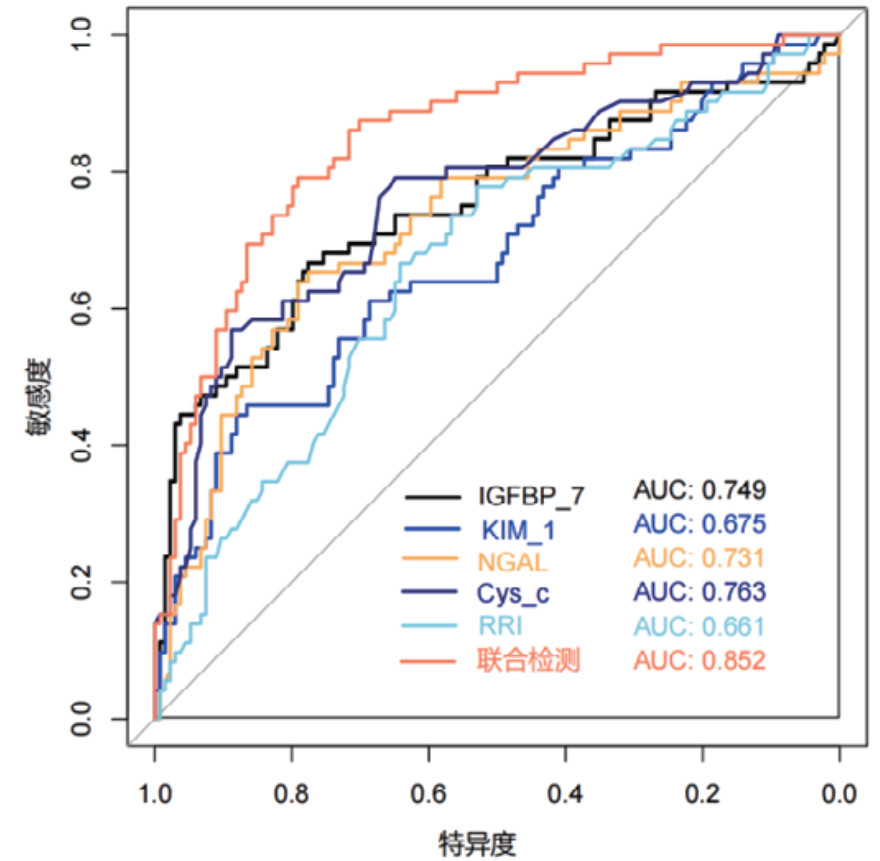

对各时间段血清Cys-C、IGFBP-7、KIM-1、NGAL和超声RRI水平及联合检测进行ROC曲线绘制,计算不同时间段联合检测的AUC值、最佳截断值、敏感度、特异度和约登指数。结果显示,联合检测0 h、12 h、24 h和48 h的AUC值分别为0.838(95%CI: 0.778~0.897)、0.852(95%CI: 0.797~0.907)、0.868(95%CI: 0.816~0.921)和0.872(95%CI: 0.820~0.924),见表 3。不同时段的AUC值提示联合检测的诊断效能要高于单项指标检测,结果见图 2、图 3、图 4和图 5。各指标各时间段的详细回归系数、标准误、P值、比值比(OR)及其95%置信区间见补充表S1。

| 检测变量 | AUC | 95%CI | 截断值 | 敏感度 | 特异度 | 约登指数 |

| 联合检测(0 h) | 0.838 | 0.778~0.897 | 0.403 | 69.44% | 82.83% | 0.523 |

| 联合检测(12 h) | 0.852 | 0.797~0.907 | 0.316 | 79.17% | 79.10% | 0.583 |

| 联合检测(24 h) | 0.868 | 0.816~0.921 | 0.309 | 81.94% | 80.60% | 0.625 |

| 联合检测(48 h) | 0.872 | 0.820~0.924 | 0.272 | 84.72% | 78.36% | 0.631 |

| 图 3 单项和联合检测12 h的ROC曲线 |

|

|

|

本研究结果显示,既往存在肾脏疾病是发生AKI的危险因素,AKI患者早期SCr和BUN水平显著高于非AKI组患者,AKI组患者的eGFR指标更低。其次,AKI组患者在0 h、12 h、24 h和48 h时间段内,血清NGAL、Cys-C、KIM-1、IGFBP-7水平及超声RRI值均高于非AKI组更高。这一结果提示,该生物标志物和RRI值的变化可以作为AKI早期诊断的敏感指标。此外,RRI值的升高也反映了肾脏血管阻力的增加和肾脏血流灌注的减少,是AKI发生的重要预测因素。但是单一指标的检测存在局限性,各项指标绘制的ROC曲线AUC值相对偏低,联合检测的AUC值优于各单项指标检测,其中联合检测48 h的AUC值最高为0.872(95%CI: 0.820~0.924),且敏感度和特异度相对较高。对各时间段联合检测指标显示各时间段预测性能比较接近,AUC值均大于0.8,提示联合检测稳定性和预测性能良好。此外,对各指标随时间变化的动态监测显示,Cys-C和KIM-1呈持续上升趋势,IGFBP-7在12 h达峰值后略有下降,NGAL在早期即显著升高并维持高水平,RRI随时间推移逐渐上升。这些指标的动态监测为AKI的早期识别、严重程度评估和预后判断提供了重要依据。不同指标在时间维度上的变化特征也反映了AKI发生发展过程中不同的病理生理机制。